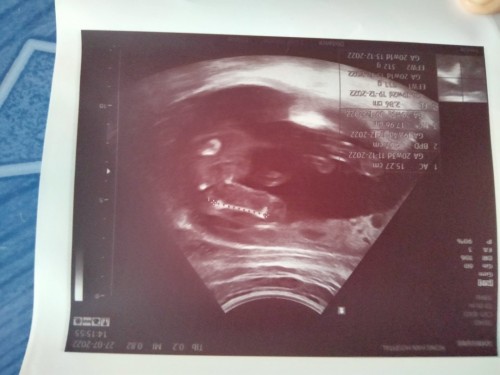

มีเเม่ๆคนไหนดูออกมั้ยคะว่าเพศอะไร

ผู้หญิง ไม่ค่อยมั่นใจเท่าไร